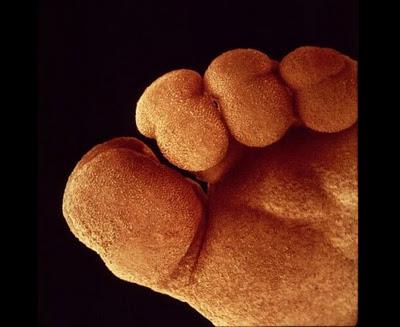

Սաղմի ոտնաթաթը